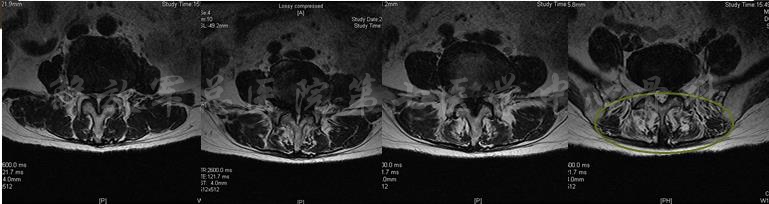

影像学检查

X线片

X线全长片:胸腰段Cobb角(L2-T11):25度;腰椎生理前凸:PI:53、PT:38、SS:15、LL:20;膝关节的屈曲畸形5度

MRI

MRI

影像学检查

X线片

颈部X线片

X线片:TL cobb 38、PI 53、SS 13、PT 40、LL 9

MRI

MRI颈4-5(左)、颈5-6(中)颈6-7(右)

矢状位MRI

轴位MRI:腰3-4(左)、腰4-5(中)、腰5骶1(右)